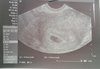

Dziewczynki jest jedna dzidzia, 1.78cm, tetno 180,![]()